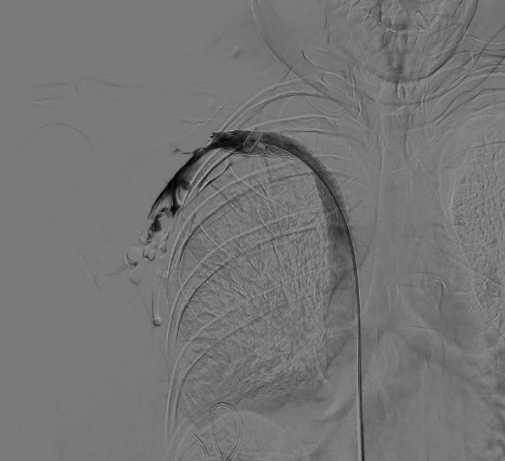

術(shù)后

DSA引導(dǎo)下精準定位釋放支架成功,再次造影,頭臂靜脈閉塞段開通,血流可順利回流至上腔靜脈,但右側(cè)鎖骨下靜脈遠心端及腋靜脈可見血栓形成,遂予以留置導(dǎo)管溶栓治療。

術(shù)后3h,患者右上肢皮膚張力明顯緩解,術(shù)后24h,右上肢腫脹明顯緩解。